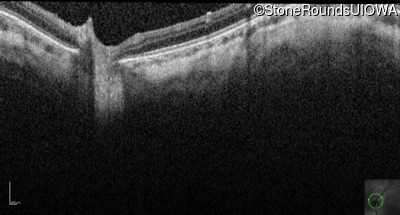

Optical Coherence Tomography - Right - 10/160 +1 sc

Exemplar / OCT Stack